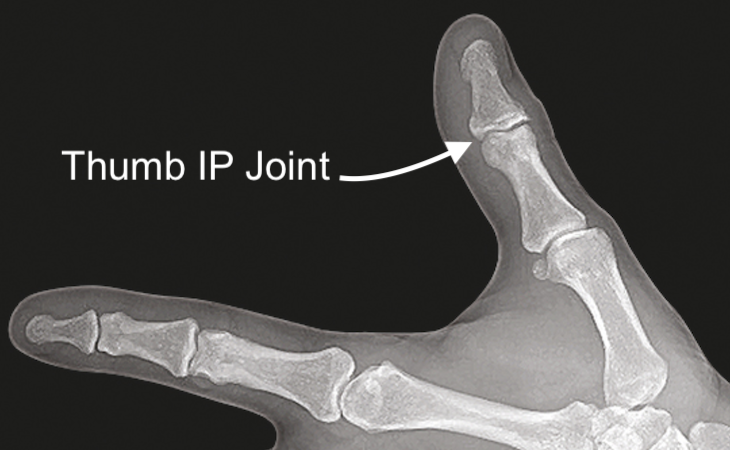

• Thumb IP Joint X-ray view

Thumb IP Joint X-ray view